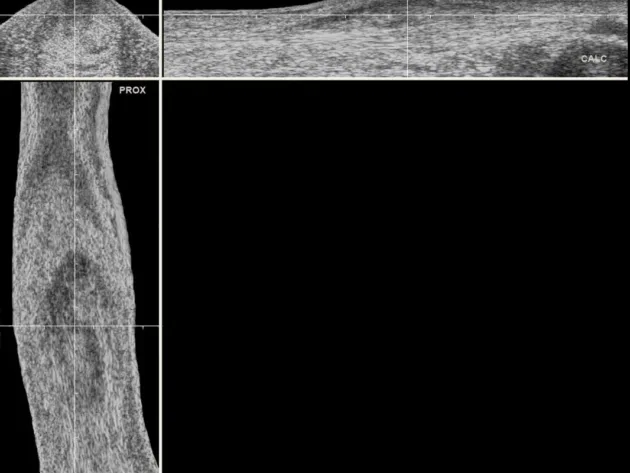

Enhance Your UTC Experience. Need accessories for your UTC Imaging system? You’ve come to the right spot!

Interested in acquiring the full UTC system? Let us craft a customized quote just for you. Click here for a personalized consultation—we’ll reach out to you shortly.